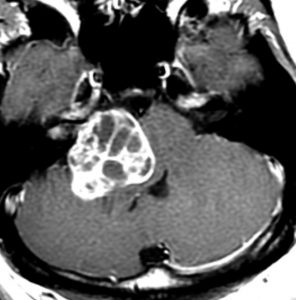

この腫瘍は脳幹部変形がとても強く,大きいので手術摘出するしか選択肢はありません

聴神経腫瘍でまず手術が必要なのは巨大なものです。この4枚の写真は私が実際に手術をした患者さんのものです。脳幹部という脳の最も大切なところが腫瘍によって圧迫されて変形しているのが特徴です。右上のものはのう胞性腫瘍なので大きさの割に手術のリスクは高くありませんが,左上のものは実質性で出血性のものですごくリスクが高い手術でした。左下のものは普通のリスク。右下のものは超高難易度のものです。